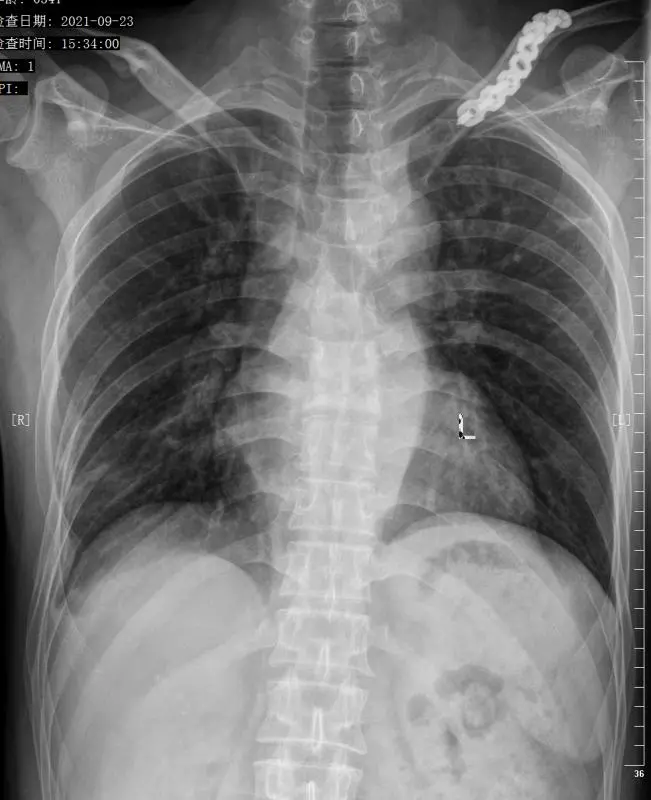

胸椎正位

胸椎x光片

诊断为:胸椎管狭窄症,考虑脊髓受压严重,手术瘫痪风险大.